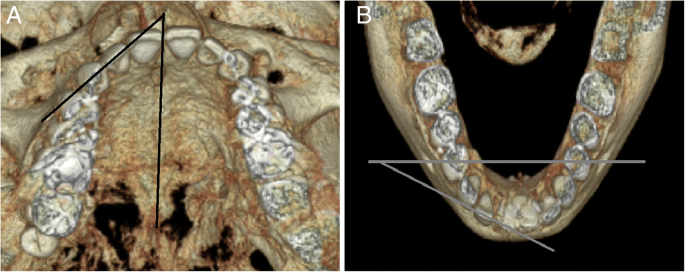

Inclination

To measure tooth inclination, patients were divided into two groups: those who underwent orthognathic surgery and those who did not. In those who underwent orthognathic surgery, the axes of the maxillary teeth were measured in the Frankfort horizontal plane and those of the mandibular teeth were measured in the mandibular plane. In those who never underwent orthognathic surgery, the axes of both the maxillary and the mandibular teeth were measured in the occlusal plane (Fig. 5).

Rotation

To assess the amount of tooth rotation, the angle between the median palatine suture and the extended line of the incisal edge in the maxilla, and the angle between the line connecting both right and left mental foramen and the extended line of the incisal edge in the mandible, was measured. Clockwise tooth rotation was defined as positive (+), while counterclockwise tooth rotation was defined as negative (−). The measured angles before and after orthodontic treatment were analyzed (Fig. 6).